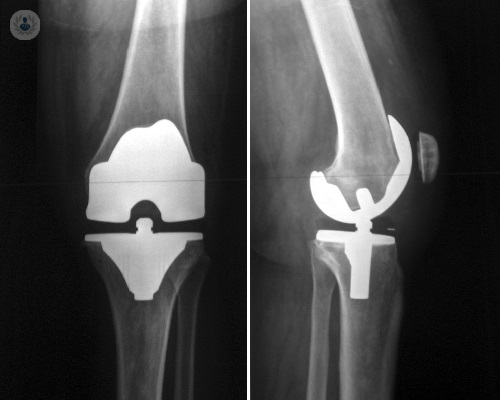

Prótesis de rodilla: beneficios y tratamiento de esta operación quirúrgica

La prótesis de rodilla o artroplastia de rodilla se basa en una técnica quirúrgica la cual se realiza cuando el cartílago de la articulación de la rodilla ha desaparecido como consecuencia del paso de los años, como puede ser por la afectación de la artrosis, o cuando ésta se ha dañado por un traumatismo.

Prótesis de rodilla para la artritis y artrosis avanzadas

La posibilidad de introducir una prótesis articular es una revolución en Traumatología y Cirugía Ortopédica, ya que permite a miles de personas recuperar la movilidad y mejorar su calidad de vida. Hablamos con el Dr. lafuente Cuenca sobre la operación para colocarlas.

Cuándo es necesaria una prótesis de rodilla y garantías que ofrece al paciente

La cirugía de reemplazo de rodilla implica la sustitución de los tejidos dañados por una articulación artificial o prótesis de rodilla. El Dr. Giménez, especialista en Traumatología, explica cuándo debe realizarse.